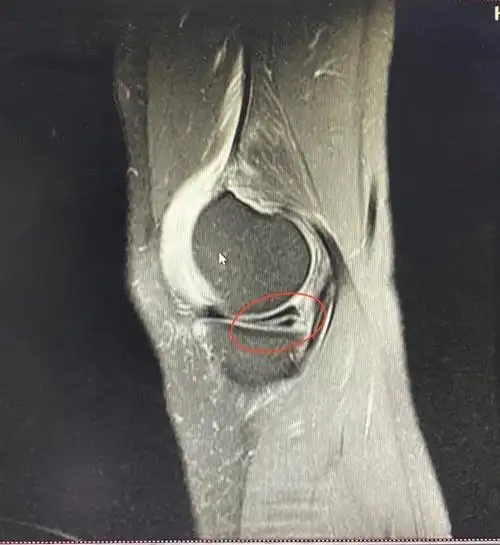

体育 正文从下图中可以清晰的看出膝盖内侧副韧带扭伤的程度,一级表示